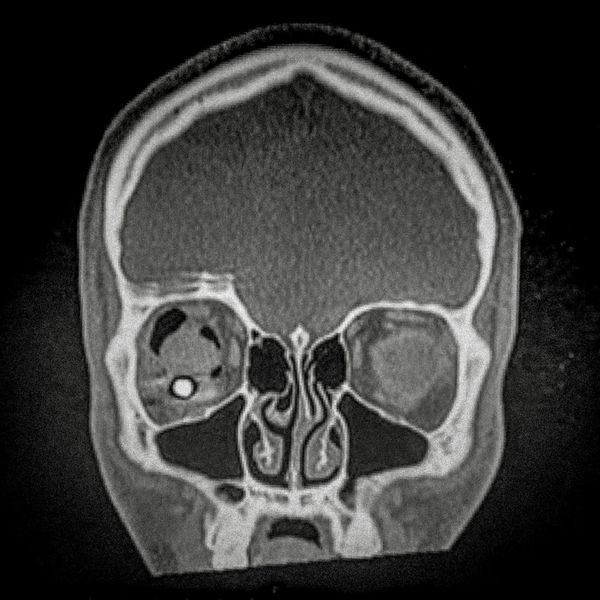

460 people have been seriously injured in their eyes, 34 of whom suffered total loss due to the indiscriminate use of pellets and tear gas bombs by the Carabineros de Chile special forces. The Carabin

460 people have been seriously injured in their eyes, 34 of whom suffered total loss due to the indiscriminate use of pellets and tear gas bombs by the Carabineros de Chile special forces. The Carabineros fired their rubber bullets and tear gas guns directly into the faces of the protesters during the Chilean social outbreak between late 2019 and early 2020. This figure has made Chile the country with the world record for eye mutilation by state and security forces.

By early March 2020, around 3,838 people had been injured and according to the Chilean Society of Ophthalmologists and human rights organizations, 460 of them ended up with serious eye complications, loss of the eyeball, and also loss of sight. This figure has made Chile a world record for eye mutilation, due to the indiscriminate use of pellets and tear gas bombs by special forces of the Carabineros, who have shot their weapons directly into the faces of the protesters.